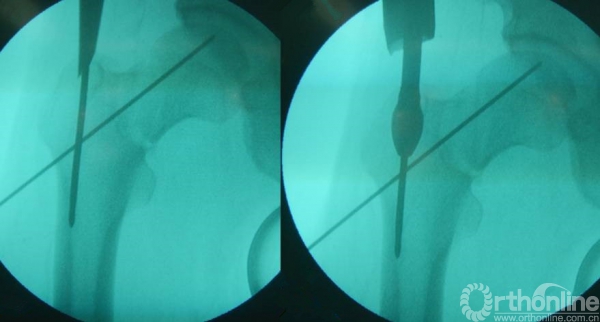

进针点选取的时候,一定注意腿的旋转。以小粗隆为参考,小粗隆稍微重叠1/3时一般为正位。

当骨折线经进钉点时,可先行头颈克氏针固定。